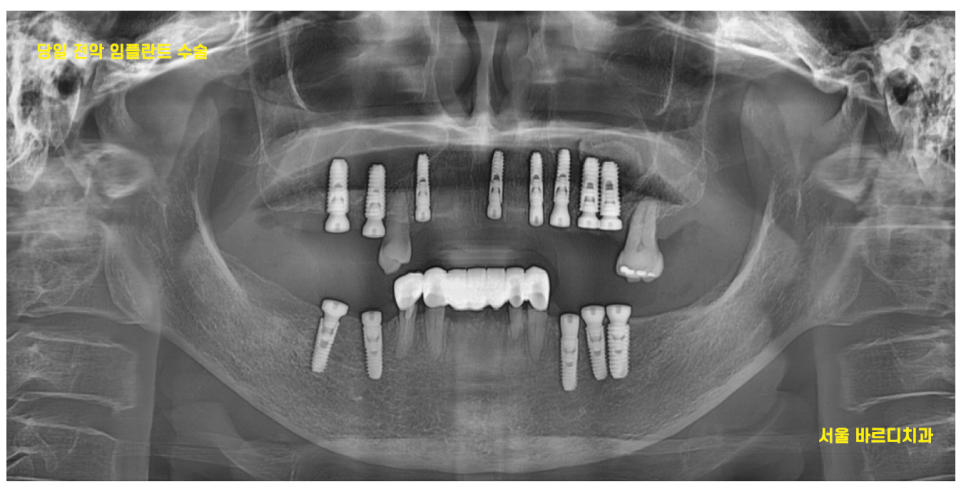

23.10.10

이를 뽑고 일주일 뒤

23.10.18

하루에 위, 아래 임플란트 수술을 진행했습니다.

하루에 많은 치아를 수술하셔야해서

수술 중 환자분의 컨디션을

계속 확인했던 기억이 납니다.

24.04.30

가이드를 통해

빠르고 정확한 수술이 가능했지만

개수가 많다보니 초집중

많이 힘드셨을텐데

무사히 끝나서 참 다행입니다~!